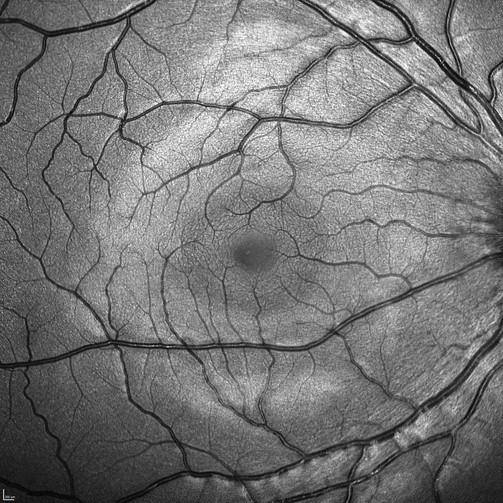

Oftalmoscopia a Laser de Varredura Confocal

O oftalmoscópio a laser de varredura confocal (cSLO) na plataforma SPECTRALIS® é uma tecnologia inovadora para examinar e obter imagens da retina e de outras estruturas oculares.

Combinando a seletividade da luz laser com a resolução precisa da varredura confocal, o cSLO oferece detalhes e clareza de imagem que não estão disponíveis na fotografia de fundo de olho.

A tecnologia cSLO não apenas oferece documentação dos achados clínicos, mas também frequentemente destaca detalhes diagnósticos críticos que não são visíveis na oftalmoscopia clínica tradicional. Como a imagem cSLO minimiza os efeitos da dispersão da luz, pode ser utilizada de forma eficaz mesmo em pacientes com catarata.